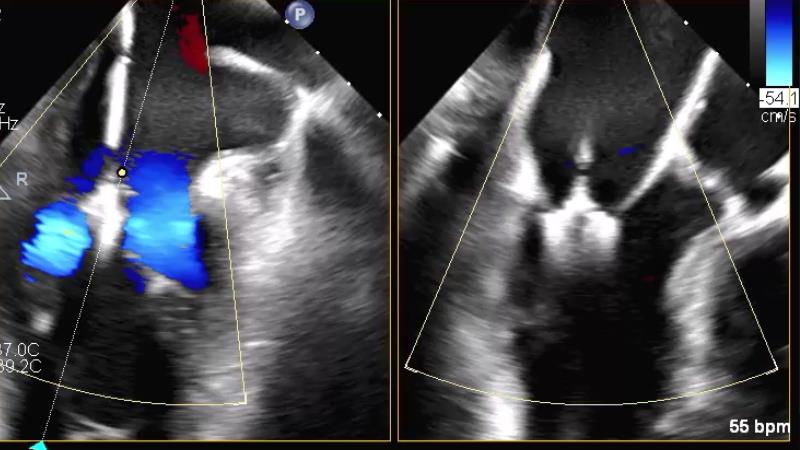

Watch this session to get an overview of a new TEER device, follow the step-by-step procedure related to initial experiences with this device for a Japanese patient with degenerative mitral regurgitation, learn about the latest data from RCT and registries, and follow discussions of challenging TEER cases!